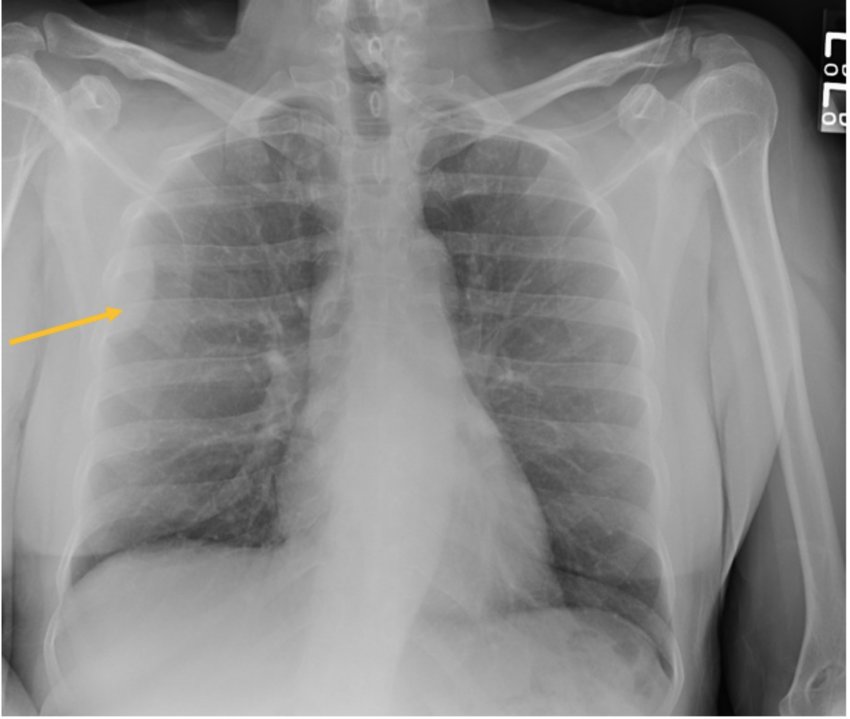

U xơ đơn độc thường hình thành ở lớp lót xung quanh bên ngoài phổi (u xơ đơn độc màng phổi). Các khối u xơ đơn độc cũng đã được tìm thấy ở đầu và cổ, vú, thận, tuyến tiền liệt, tủy sống và các vị trí khác.

Bác sĩ sử dụng một trong các xét nghiệm hình ảnh sau để chẩn đoán u xơ đơn độc:

- Chụp X-quang